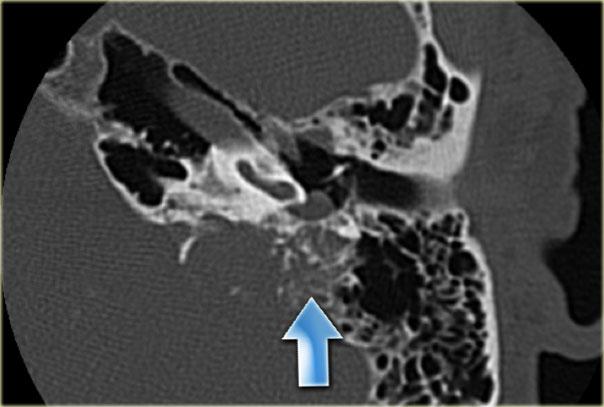

Bên trái là hình ảnh của một bệnh nhân nam 58 tuổi.

Mũi tên màu xanh chỉ cống ốc tai đi về phía ốc tai.

Hình ảnh này có thể bị nhầm lẫn với đường gãy xương (mũi tên).

Lưu ý có hình ảnh mờ đục của hòm nhĩ và các tế bào khí xương chũm.